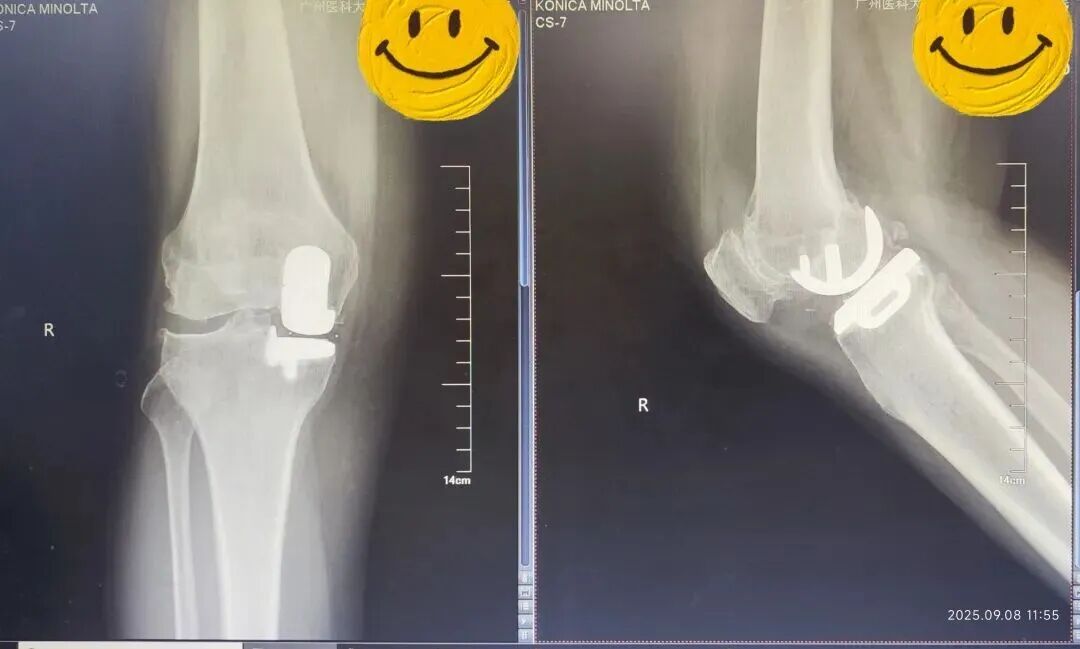

术前(左)术后(右)X线光片对比

在麻醉科配合下,陈东峰手术团队清除了增生的滑膜组织,去除了骨赘,对关节进行了适当松解,术中发现关节面磨损严重,软骨下骨暴露,内侧半月板后角脱位。医生精心安置了人工关节假体,替代了已经损坏的关节面。

手术后无需放置引流管,多模式镇痛下,患者麻醉恢复后即可下地完全负重行走,温女士终于摆脱了困扰她十年的膝痛问题。